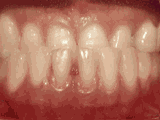

Underbite: Lower front teeth in front of upper teeth.

Patient's underbite was causing her jaw joint discomfort and excessive wear patterns on her teeth. After thirty months of treatment starting at age thirty-two, she now finds smiling and chewing much easier.